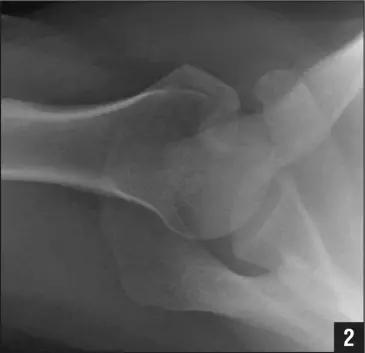

5. Hoffa 骨折

指股骨远端冠状面的骨折。

病例 1:一般股骨髁间、髁上粉碎骨折中含 Hoffa 骨折的不少见,但单纯后髁骨折则很少见。

正位片

侧位片

水平位 CT

第 2 例

第 3 例